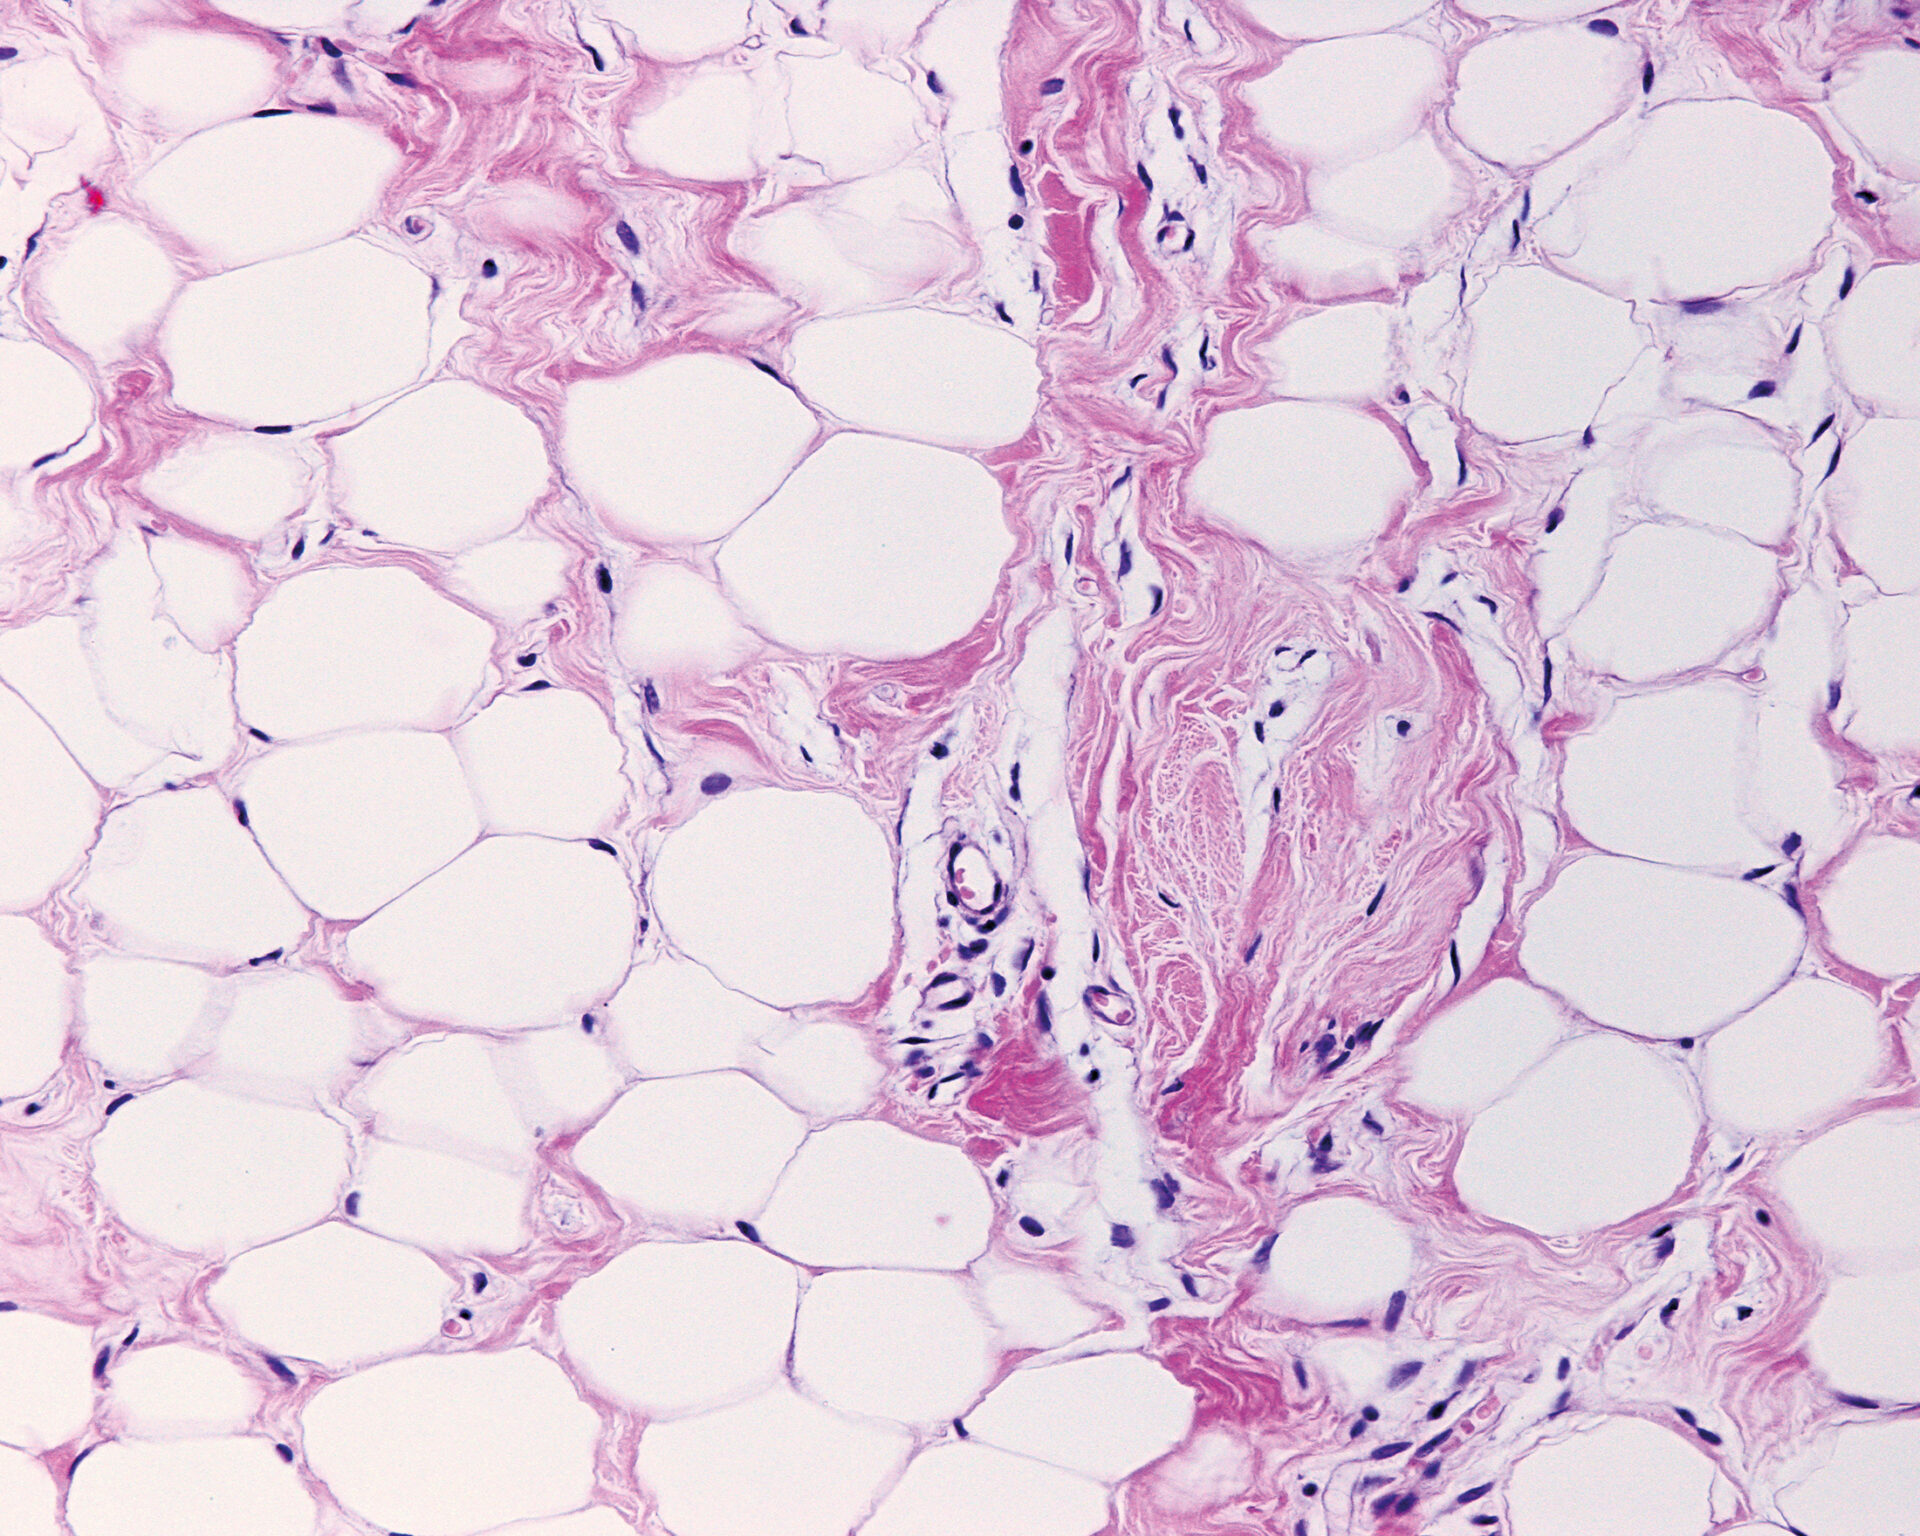

Beim Lipödem handelt es sich um eine schmerzhafte, überproportionale Fettvermehrung bei Frauen; an Beinen und Armen, sowie Hüften und Gesäss. Seit einigen Jahren ist das Lipödem im ICD-Katalog offiziell als Krankheit klassifiziert. Die Diagnose wird anhand von klinischen Kriterien gestellt. Für eine Liposuktion erfolgt in der Schweiz aktuell eine Kostenübernahme, wenn die mit dem Lipödem verbundenen Schmerzen ungenügend auf intensive konservative Therapie (Kompression und Manuelle Lymphdrainage) ansprechen, und eine vertrauensärztliche Empfehlung ausgesprochen wird. Neben operativen und konservativen Verfahren zählen Ernährungsumstellung und Bewegungsintensivierung zu den weiteren Therapiesäulen.